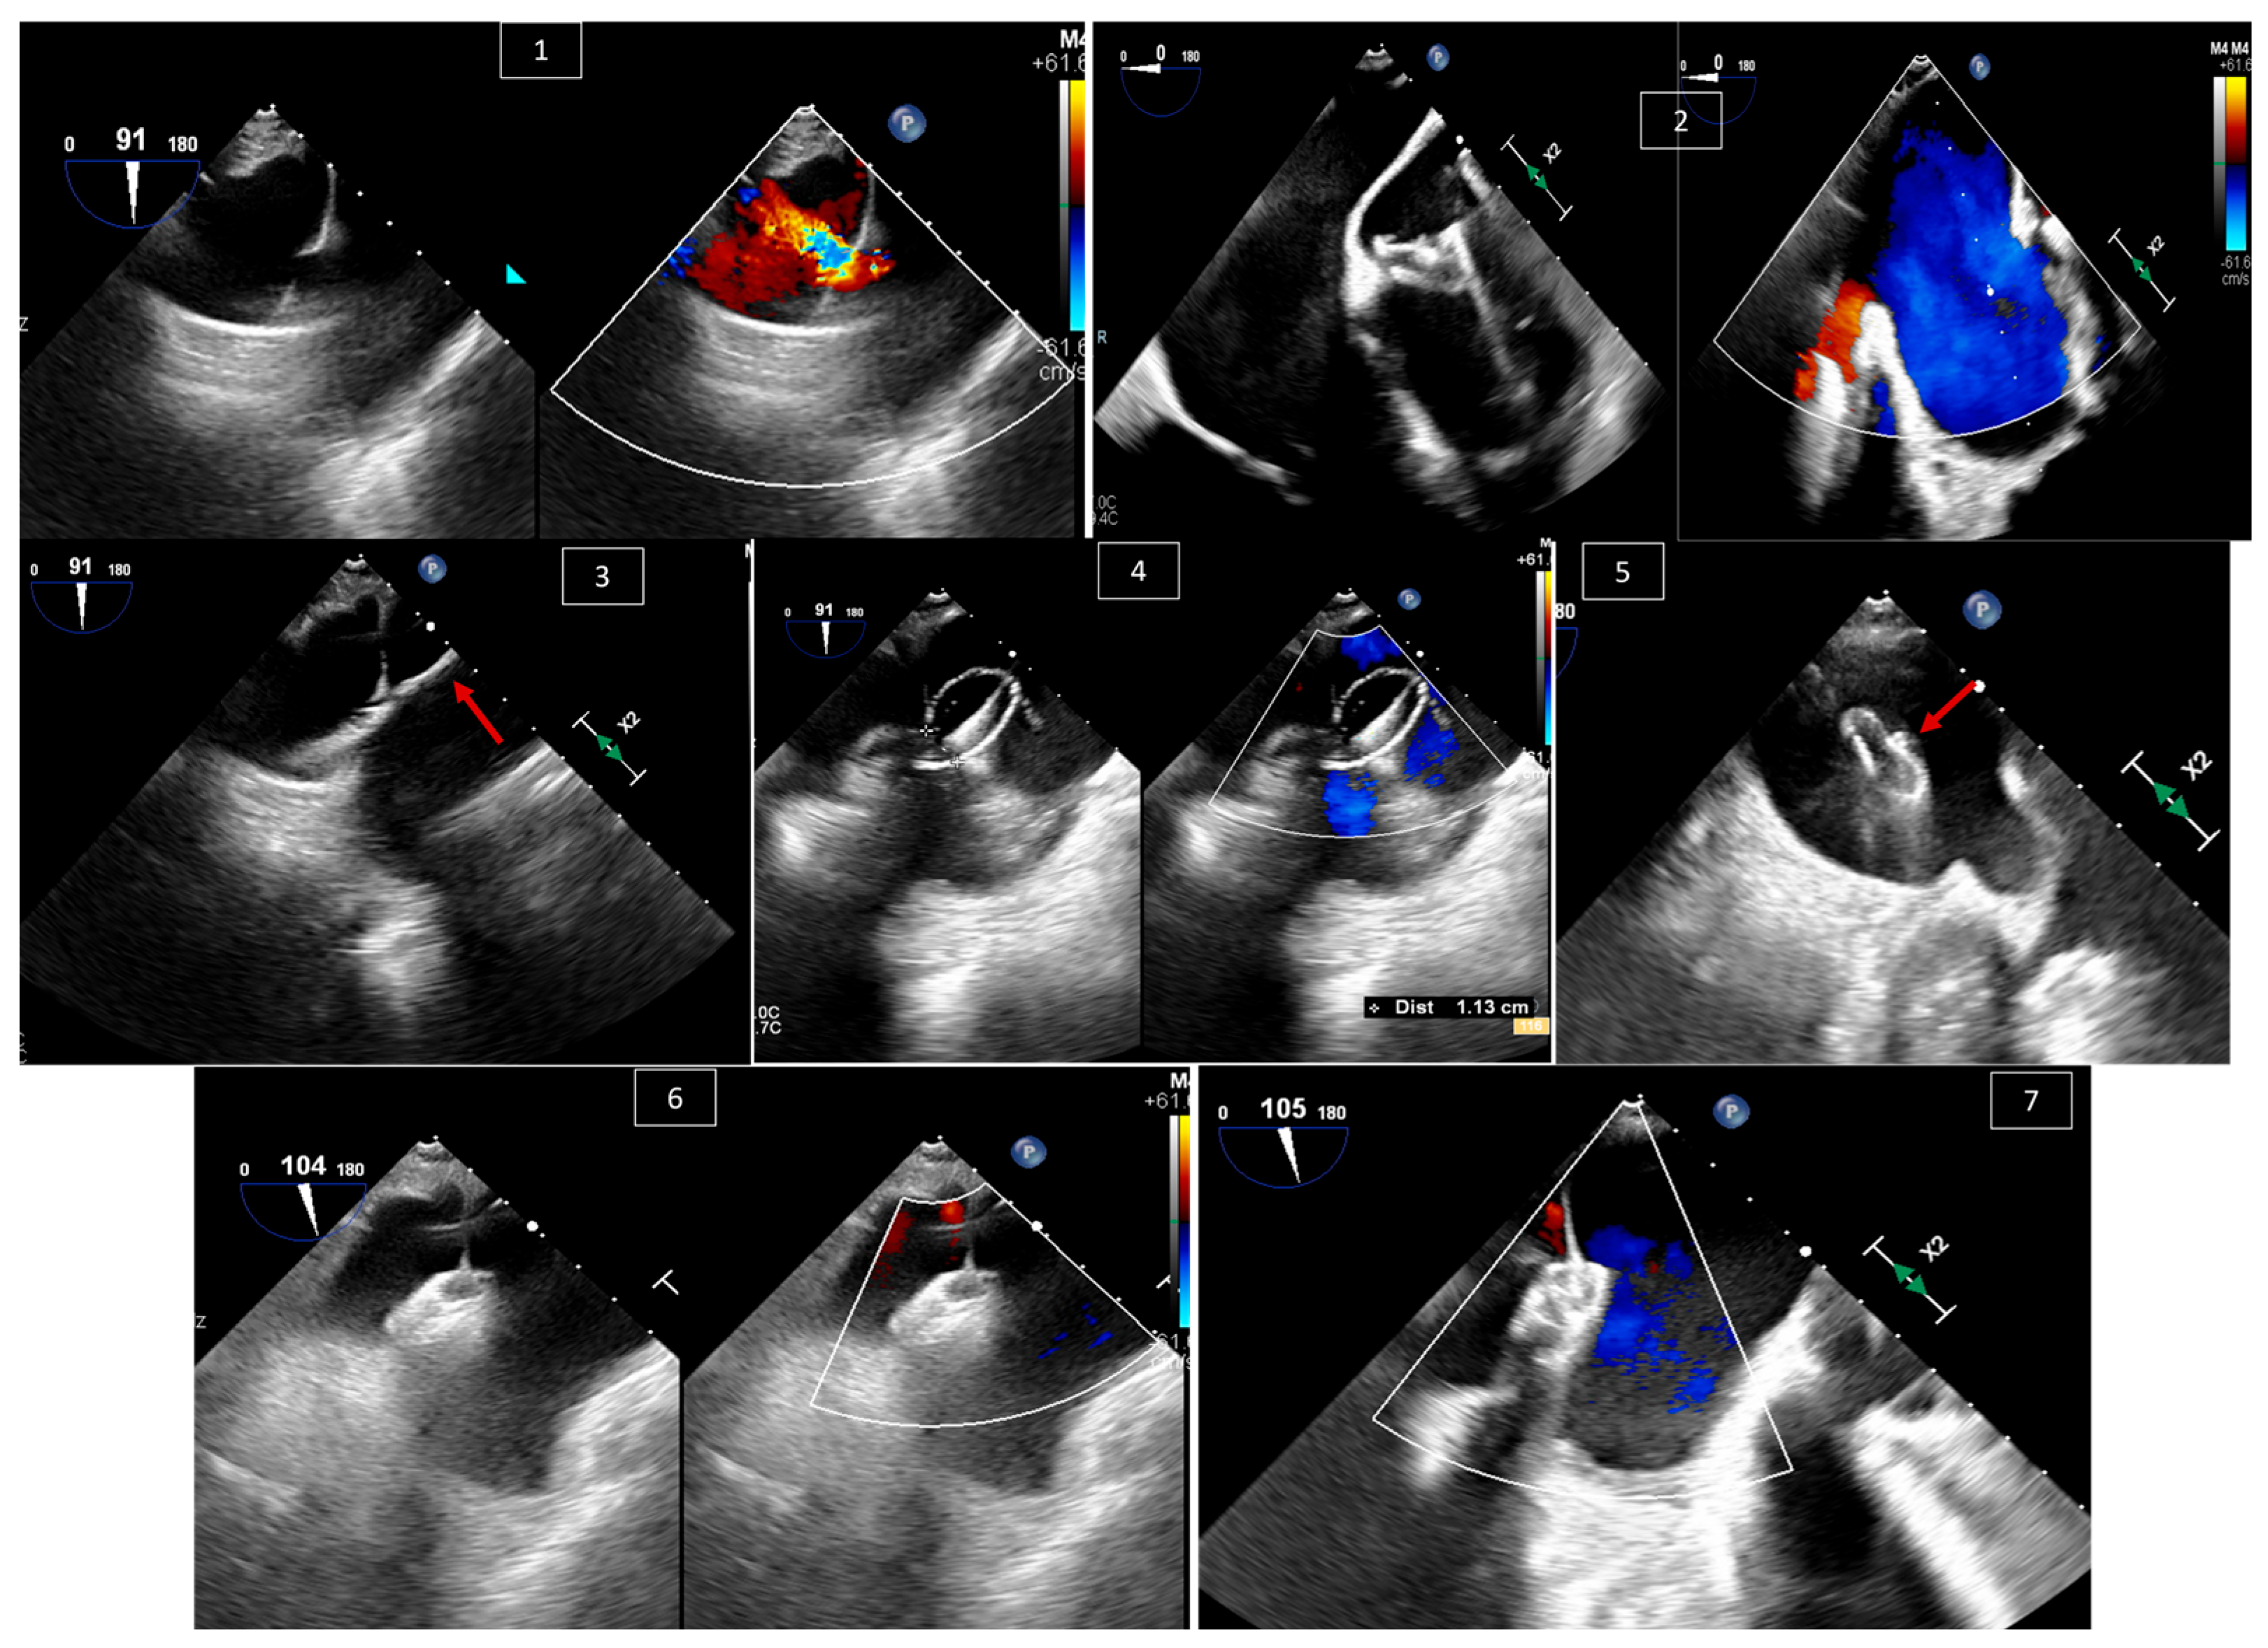

6. Baffle Complications in Atrial Switch Operations